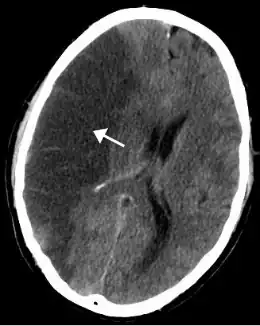

Hersendeel met infarct in het ACM-stroomgebied